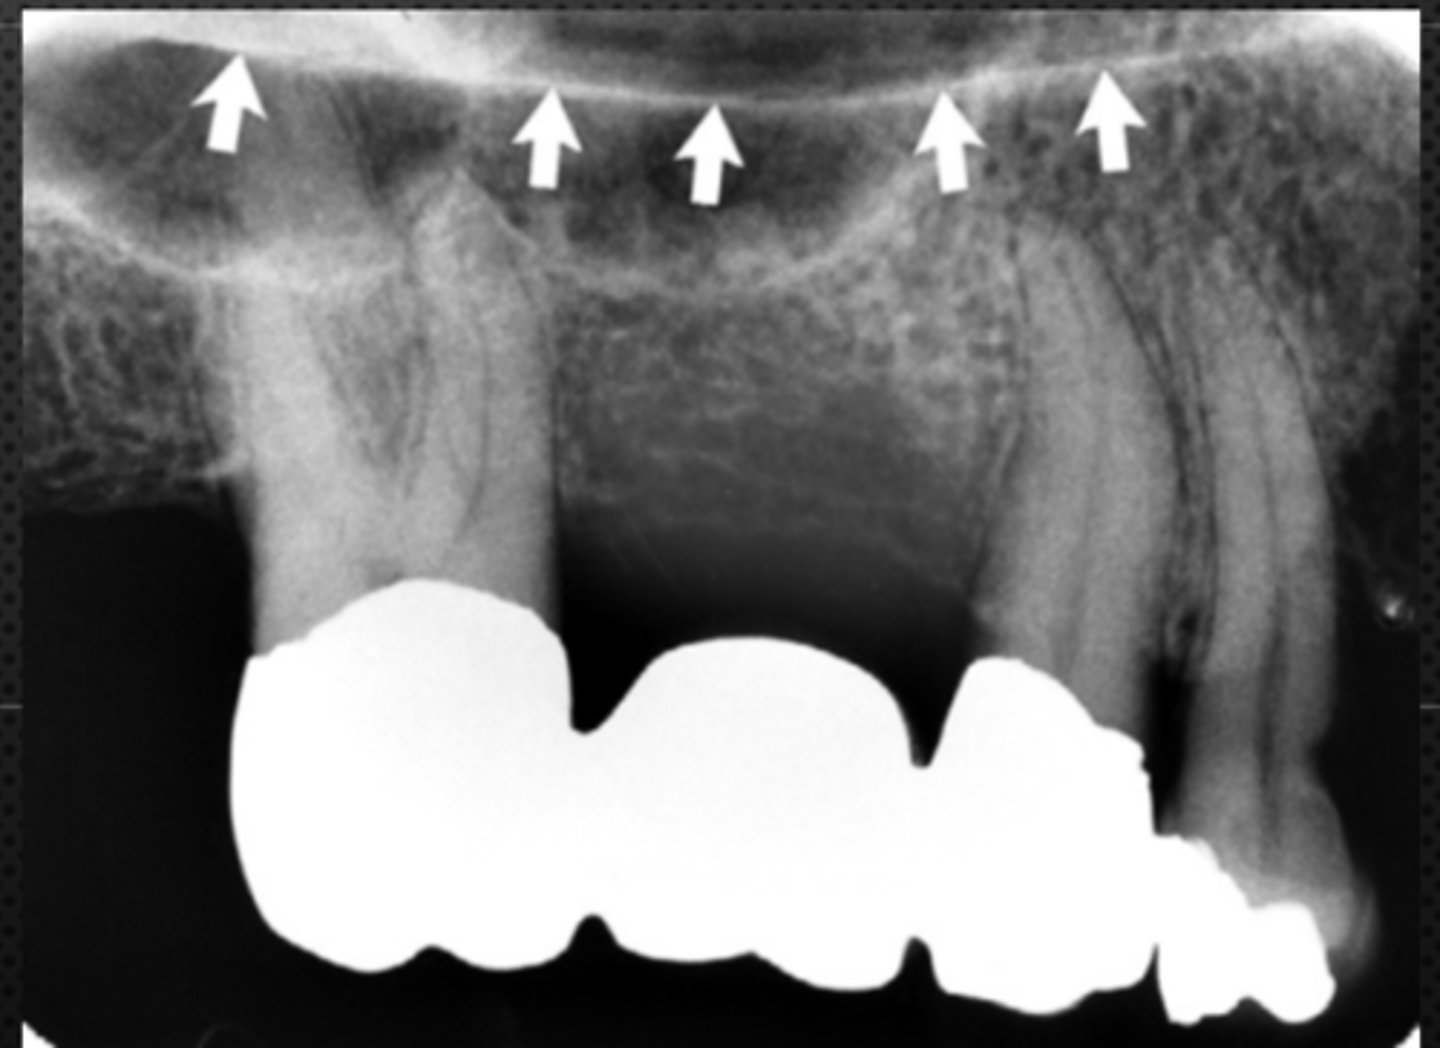

New cards

Black arrow - Floor of the nasal cavity

White arrow- maxillary sinus

Identify the structures

<p>Identify the structures</p>

15

Maxillary sinus

Identify the structure

Floor of maxillary sinus

Name the curved, radiopaque line that superimposes the roots of the teeth indicated by #7.

Floor of the maxillary sinus

Name the line indicated by arrows labeled #2.

Sinus septum

Name the straight (slightly curved), radiopaque structure indicated by the arrows.